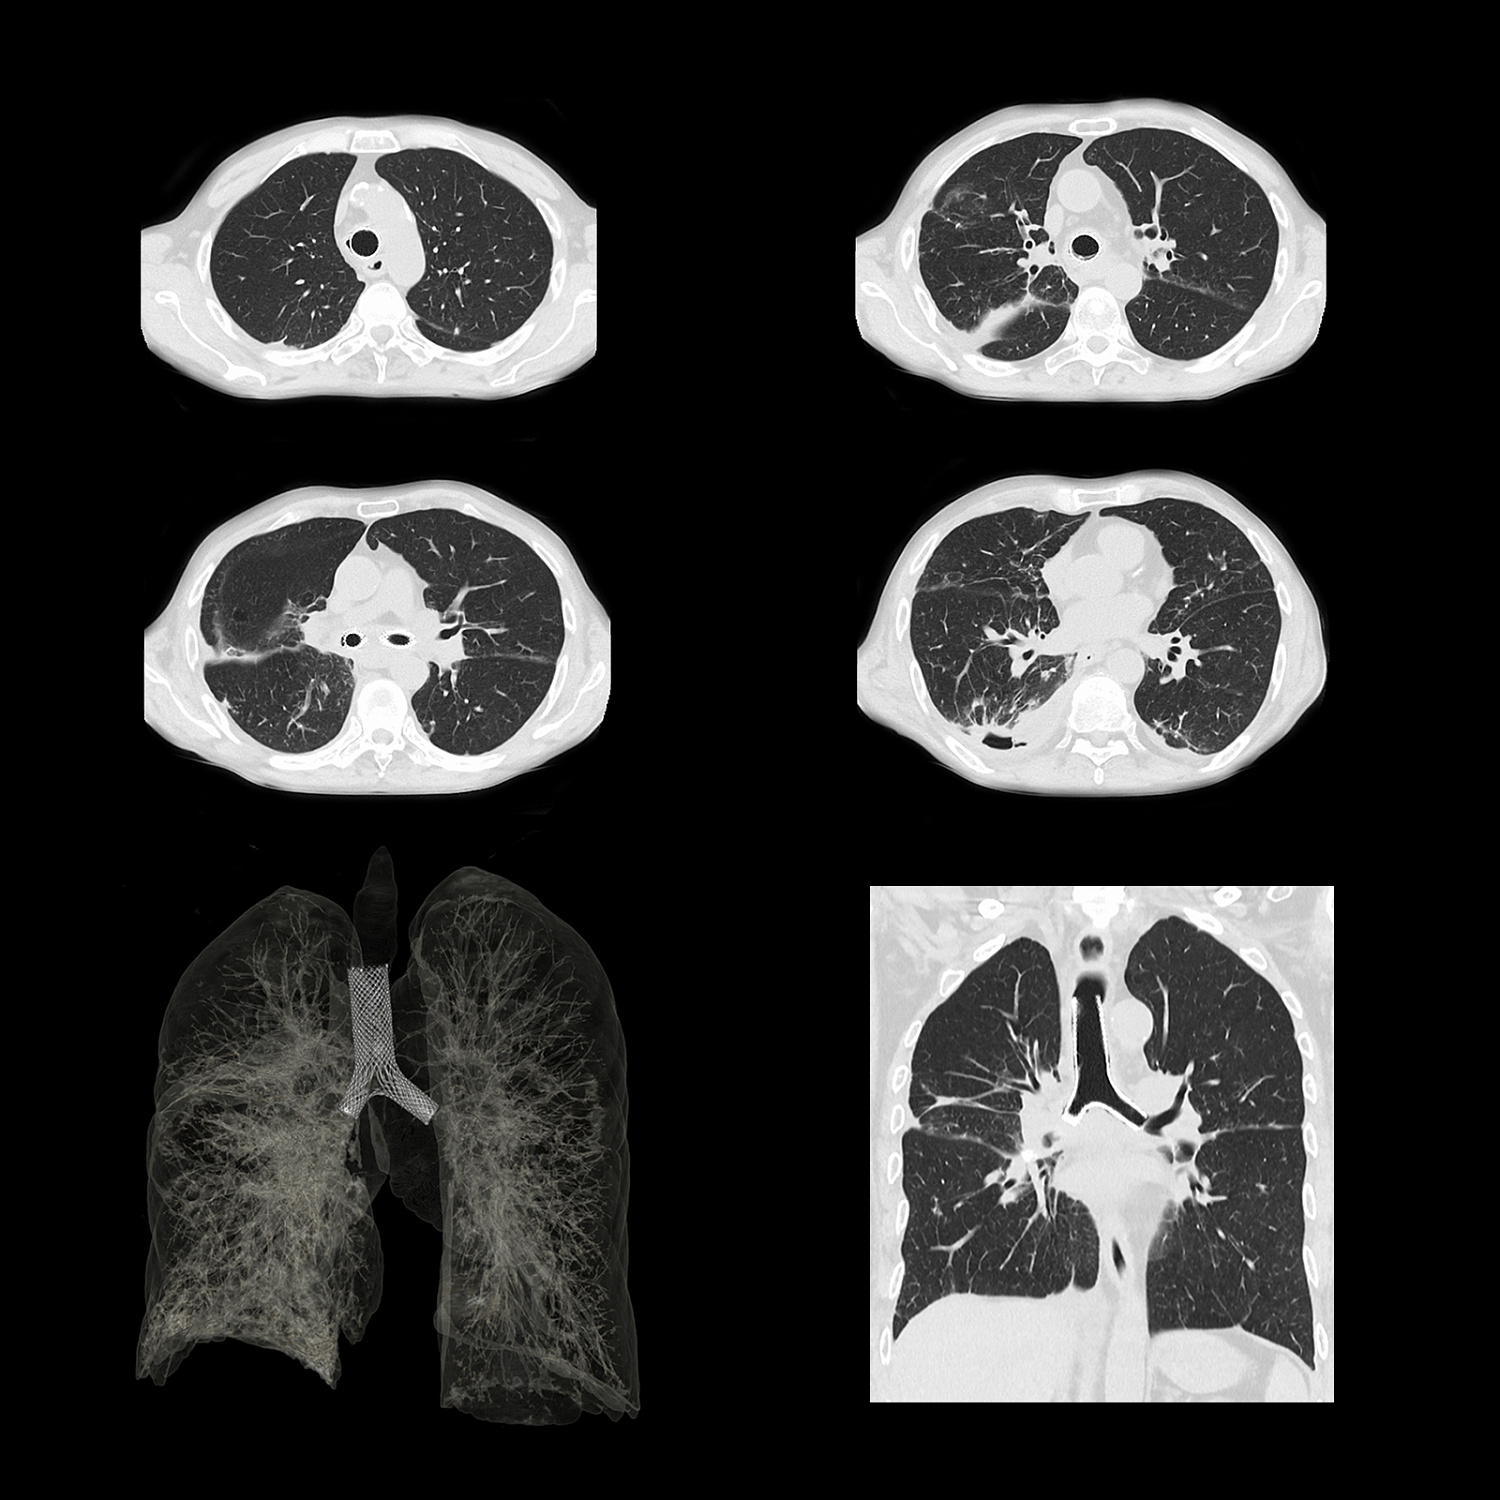

Фильтр SilverBeam

SilverBeam, энергетический фильтр, формирующий луч, использует свойства серебра по ослаблению фотонов для выборочного удаления фотонов низкой энергии из полихроматического рентгеновского луча, оставляя энергетический спектр, оптимизированный для скрининга рака легких.

КТ-скрининг рака легких при уровнях доз, приближающихся к обычной рентгенографии

Разработанный для работы в сочетании с AiCE, SilverBeam предоставляет улучшенные, высококачественные, малошумящие КТ-снимки скрининга рака легких при дозе облучения порядка типичного рентгенологического исследования грудной клетки.

SilverBeam с AiCE можно использовать для надежной организации службы скрининга рака легких в вашей больнице.

Расширенный интеллектуальный модуль Clear-IQ Engine (AiCE)

КТ-реконструкция, в которой используются инновации глубокого обучения, чтобы соответствовать пространственному разрешению и малошумным свойствам усовершенствованных итеративных реконструкций на основе моделей для получения высококачественных изображений без ущерба для скорости или дозы.

- Малый шум

- Естественная текстура изображения

- Четкое высококонтрастное разрешение

- Четкая низкоконтрастная детектируемость